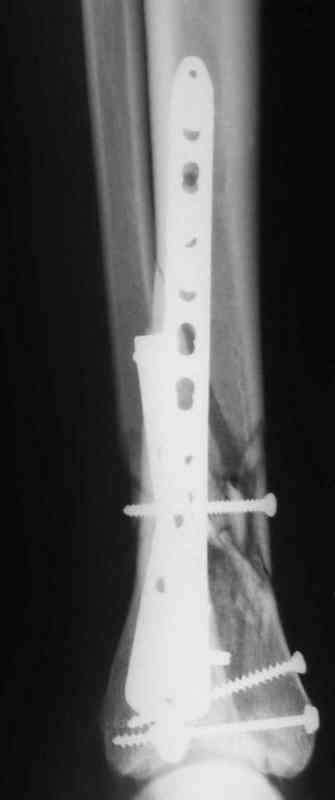

В настоящее время больной в реанимации по поводу Черепно Мозговой Травмы и состояние улучшается. Запланировал ушивание раны в пятницу, если позволит состояние мягких тканей и при отсутстви отека возможно удастся просунуть перкутанномедиальную пластину.

Да кстати нашёл похожий случай для пилона.Малоинвазивная дистальная пластина LCP у вас я думаю есть опыт их использования ну очень хорошая. Очень стабильно получается.